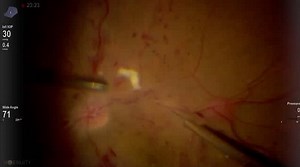

Preparing Subretinal tPA Injection - Eyetube

Subretinal tPA Injection - Eyetube

Subretinal Injection of tPA Myopic Staphyloma - Eyetube

Subretinal tPA for the Treatment of Subretinal Hemorrhage - Eyetube